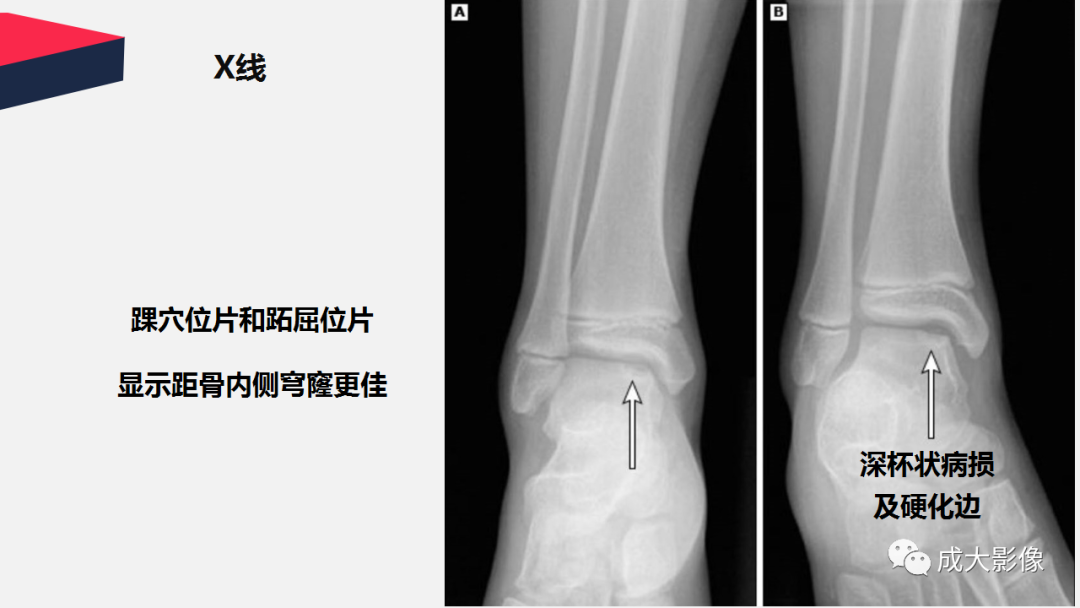

【PPT】剥脱性骨软骨炎-2